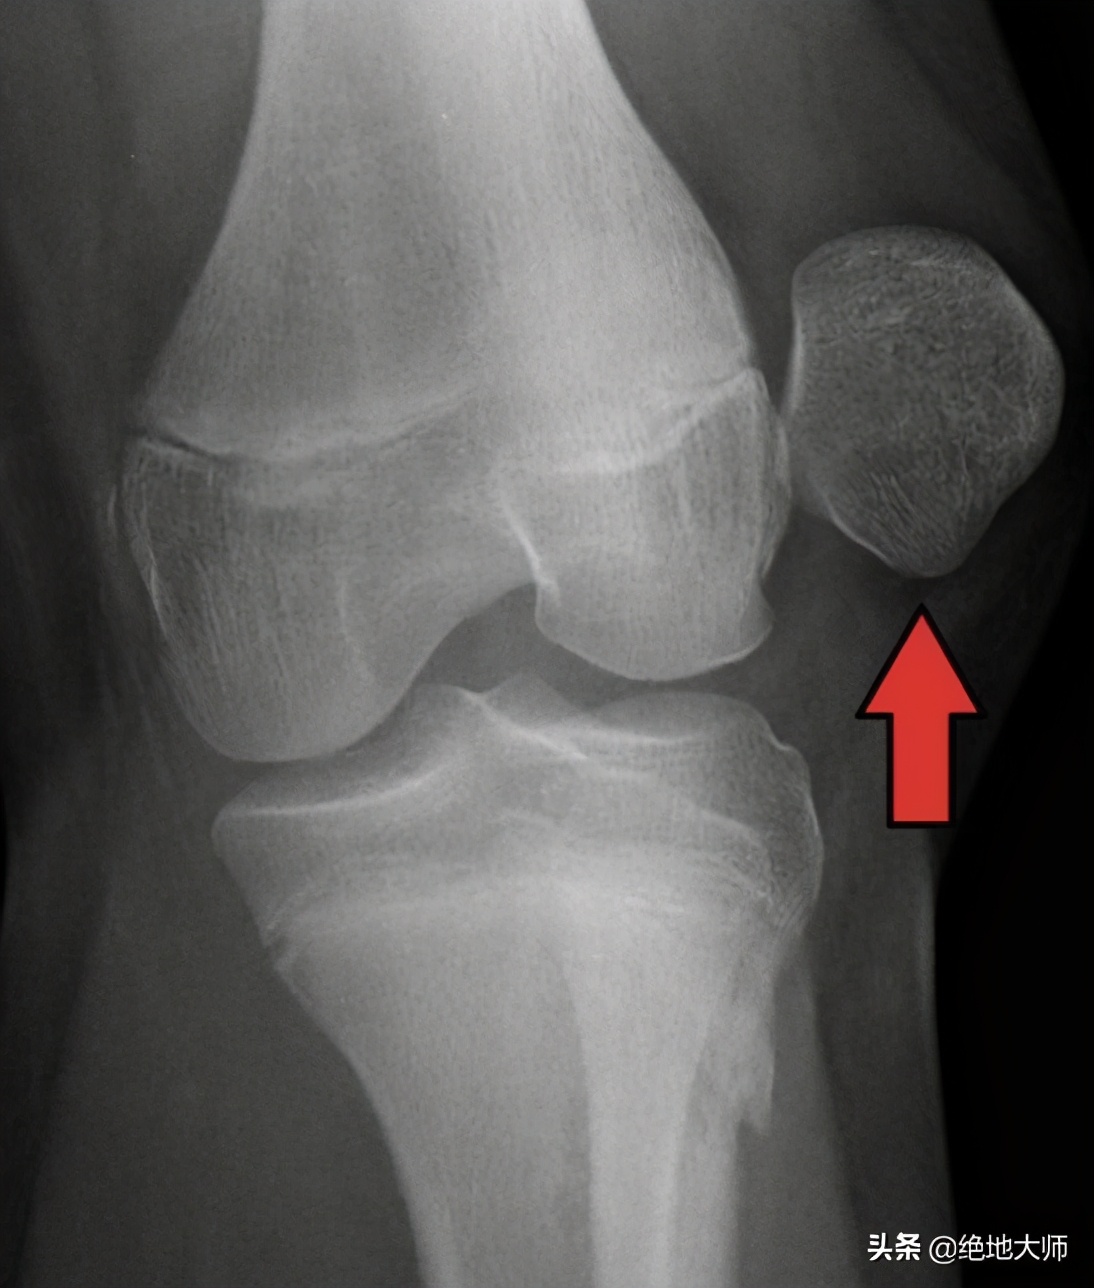

8. 创伤性膝关节疼痛的评估与神经调控康复治疗

没有一套常规治疗能够有效治疗各种原因的膝关节疼痛。虽然针刺是治疗膝关节疼痛的一种非常有效的方法,但如果不正确了解膝关节疼痛的不同病因,治疗效果将不一致或没有效果。在本课程中,你将学习创伤性(下期非创伤性)膝关节疼痛的临床分型、应用解剖、骨关节试验,以及功能评估和神经调控康复方案。

课程大纲:

膝关节疼痛的分类;

膝关节疼痛的应用解剖;

软组织修复的原则;

创伤性膝痛的骨关节试验;

急性膝痛的神经调控方案。